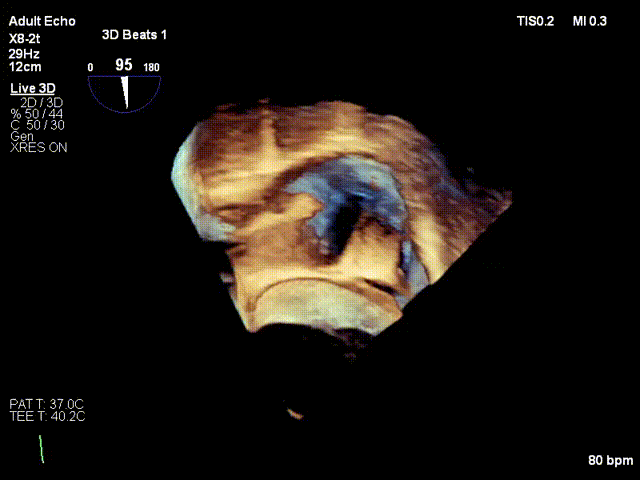

1. 术中基线评估三尖瓣反流程度

术中基线